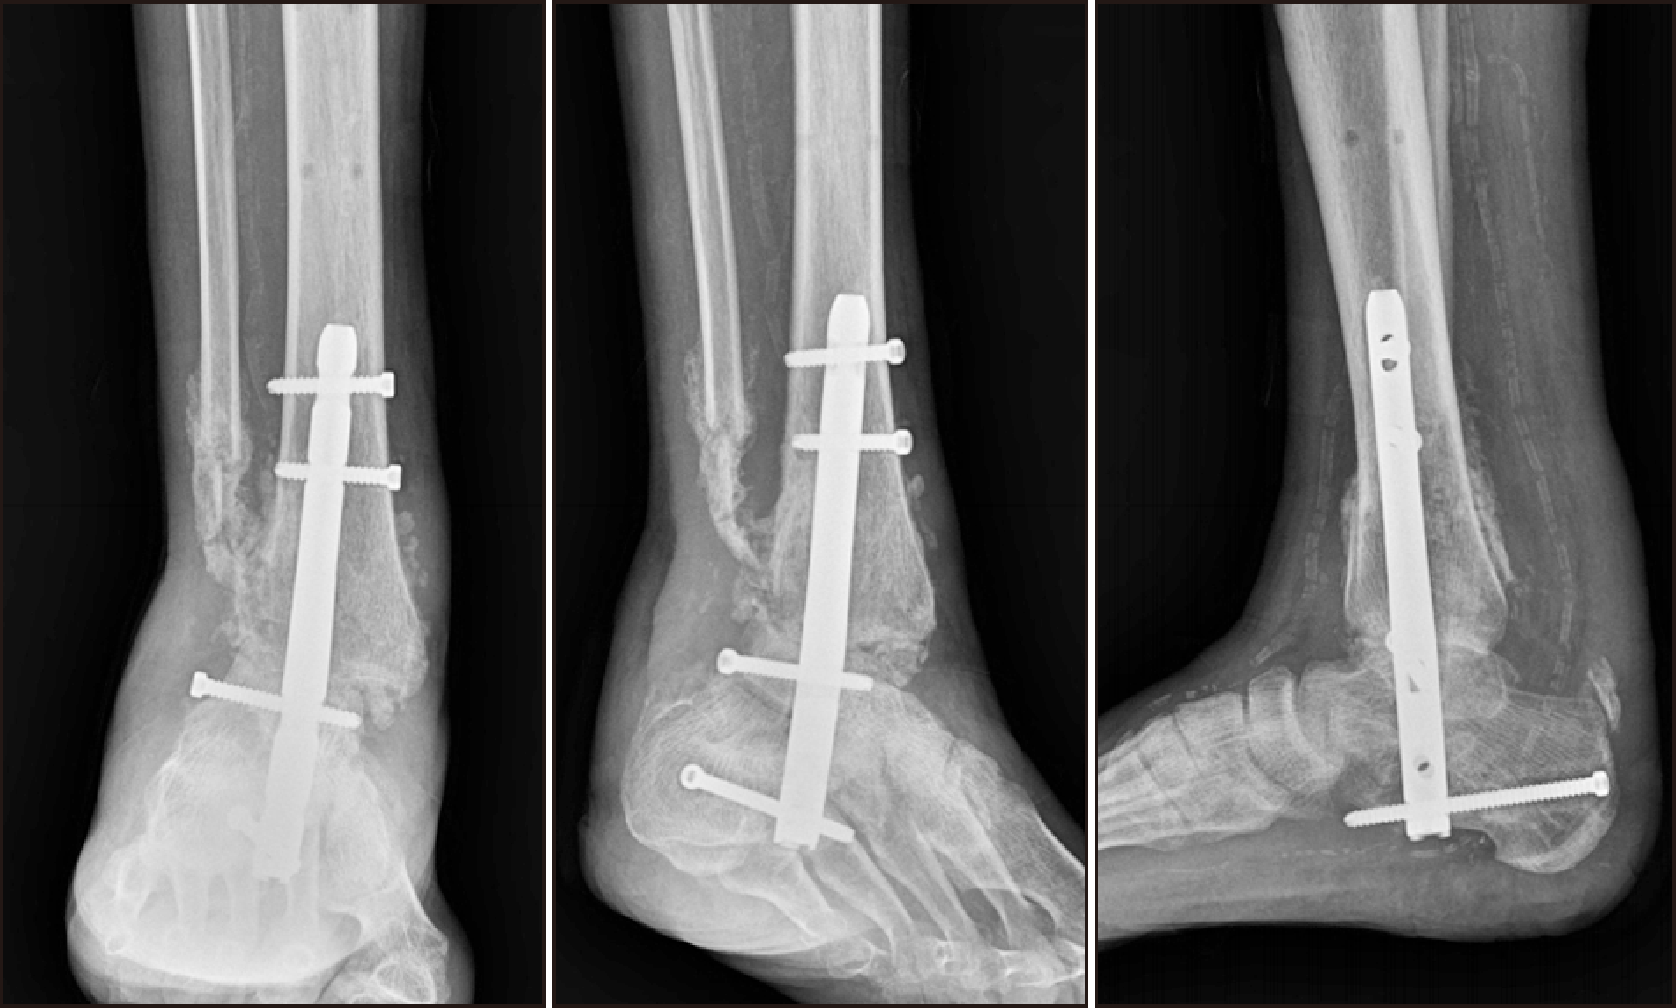

During outpatient follow-up, 8 months post-surgery, the patient exhibited signs of fever and operation site infection, along with evidence of metal loosening, necessitating hospital admission (Fig. 12). Despite the arduous clinical journey, the patient declined the option for a below-knee amputation. Given the ongoing complications, a decision was made to perform comprehensive surgical intervention. In light of evidence of implant-associated infection, metal removal was performed and anti-cement arthroplasty was carried out (Fig. 13). Three months after, this involved the insertion of a vancomycin-mixed cement filling, TTC fusion using a proximal humeral internal locking system (PHILOS) plate (DePuy Synthes) on the lateral side, and additional fixation using a 6.5 TCS (threaded cannulated screw) (Fig. 14).

Follow-up visits were promising: 2 months after TTC fusion, the patient could walk short distances without difficulty (Fig. 15). The most recent follow-up, 2 years post-TTC fusion, showed no major complications. The patient was able to engage in light daily activities. Radiograph images confirmed well-maintained fusion, with the exception of a broken screw in the second from the distal portion (Fig. 16).

Figure 13

Post-operation radiograph following metal removal and anti-cement arthroplasty due to findings of implant-associated infection.

Figure 14

(A) Post-operation radiograph showing vancomycin-mixed cement filling, TTC fusion using a proximal humeral internal locking system (PHILOS) plate on the lateral side, and additional fixation with a 6.5 threaded cannulated screw. (B) Day 10 post-revision TTC fusion medial and lateral clinical pictures. TTC: tibiotalocalcaneal.